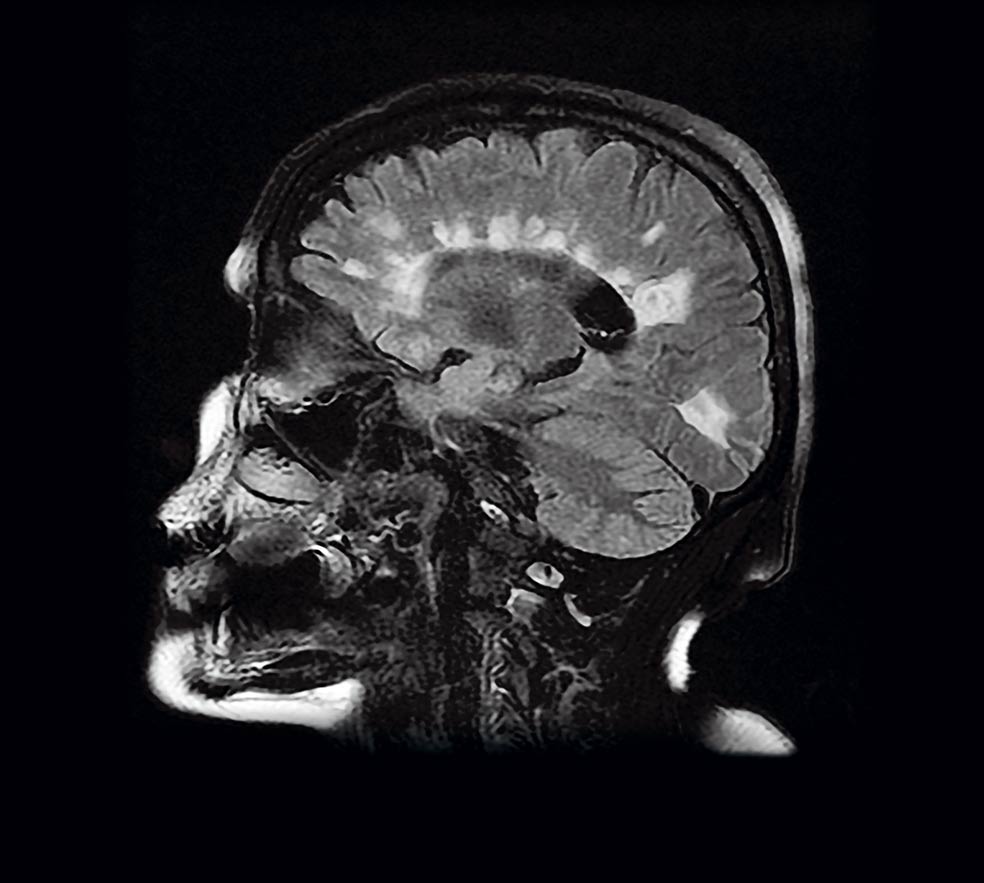

Las placas. La resonancia magnética es una de las pruebas que se utilizan para observar si hay lesiones compatibles con la esclerosis múltiple. Se conocen como 'placas' y son las manchas blancas  que aparecen en la imagen.